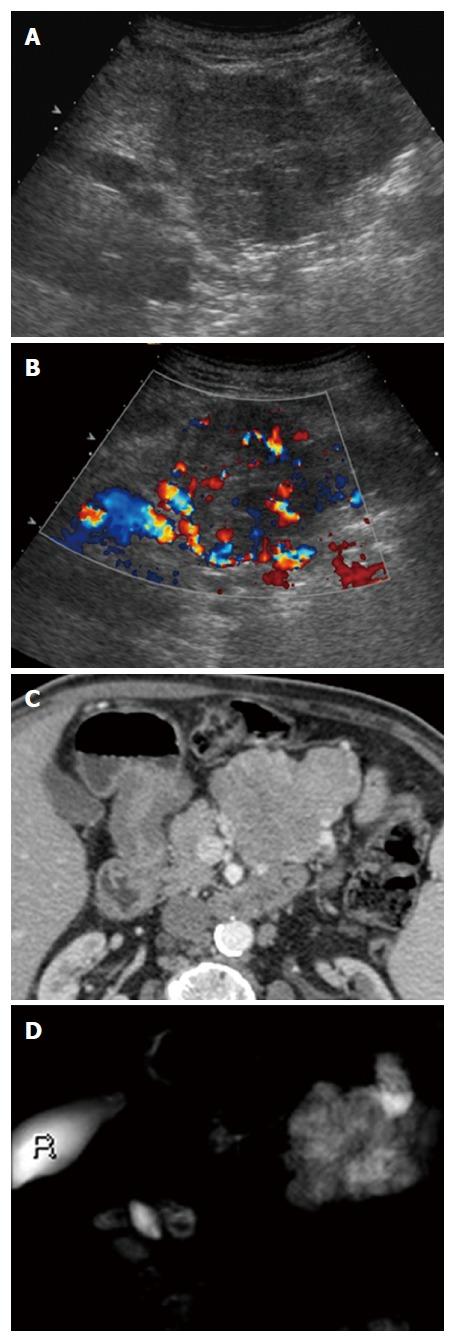

Female predominance is seen with most SPNs presenting asymptomatically in the 5 through 7 decade. Mean lesion size was 38.7 mm, 98% were single, 44.2% cystic, 46% mixed cystic and solid, and 94% hypoechoic on B-mode ultrasound. Vascular patterns and contrast-enhancement profiles are described as hypervascular and hyperenhancing.

大多数 SPN 以女性为主,无症状表现,发病年龄在 5 至 7 十年代。平均病变大小为 38.7 毫米,98%为单发,44.2%为囊性,46%为囊实性混合,94%在 B 模式超声下呈低回声。描述了血管模式和对比增强特征为富血管性和高增强性。